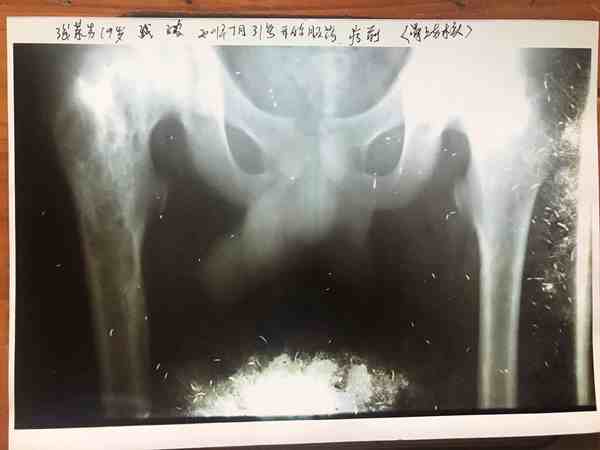

2、非手术治疗:骨结核,股骨头坏死,骨伤后,骨质不长,《骨细胞可快速生长》。目前在医学界还没有发现治疗骨病这种速度,请看下面图片检查结果对比。颈椎病引起的头昏,头痛、腰椎病,腰椎手术后遗症,一至2天见效。